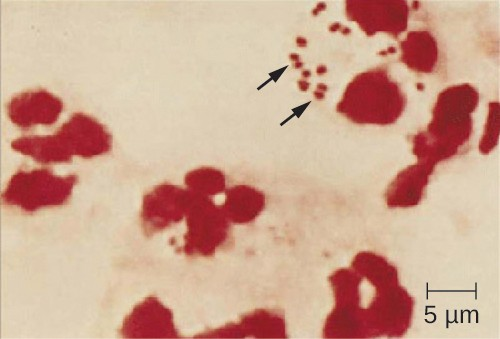

Because meningococcoal meningitis progresses so rapidly, a greater variety of clinical specimens are required for the timely detection of N. meningitidis. Required specimens can include blood, CSF, naso- and oropharyngeal swabs, urethral and endocervical swabs, petechial aspirates, and biopsies. Safety protocols for handling and transport of specimens suspected of containing N. meningitidis should always be followed, since cases of fatal meningococcal disease have occurred in healthcare workers exposed to droplets or aerosols from patient specimens. Prompt presumptive diagnosis of meningococcal meningitis can occur when CSF is directly evaluated by Gram stain, revealing extra- and intracellular gram-negative diplococci with a distinctive coffee-bean microscopic morphology associated with PMNs (Figure 21.6).

N. meningitidis (arrows) associated with neutrophils (the larger stained cells) in a gram-stained CSF sample.

Figure 21.6 N. meningitidis (arrows) associated with neutrophils (the larger stained cells) in a gram-stained CSF sample. (credit: modification of work by the Centers for Disease Control and Prevention)